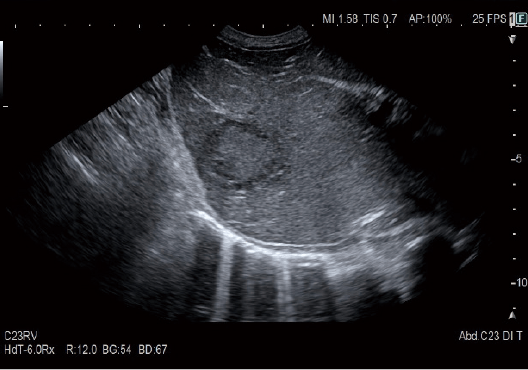

Gerçek Zamanlı Doku Elastografisi (RTE)

RTE, doku gerinimini gerçek zamanlı olarak değerlendirir ve doku sertliğini renk haritası olarak görüntüler. Uygulama, meme de dahil olmak üzere çok çeşitli klinik alanlarda doğrulanmıştır ve karaciğer fibroz evrelemesinin tahmini elastisite değerini hesaplamak mümkündür.